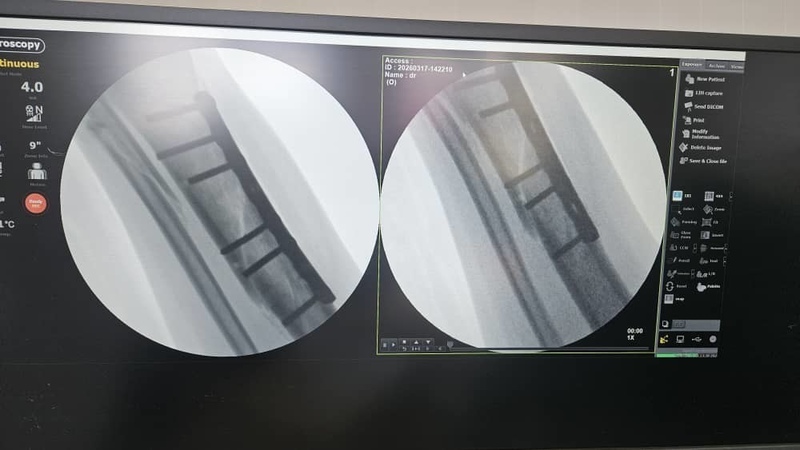

AKIPRESS.COM - Since the opening of the pediatric orthopedics department at the National Maternal and Child Health Care Center, more than 35,000 children have received consultations and 3,000 surgeries have been performed, the Ministry of Health reported on April 7...